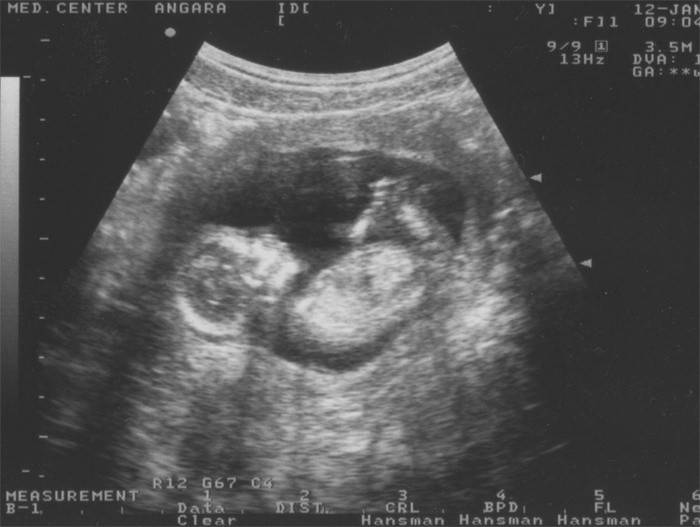

Ultrassonografia às 13 semanas

Normalmente, no período de 12 a 14 semanas, é realizada a primeira ultrassonografia planejada do feto e do útero, que mostrará a condição do futuro bebê, a posição e o funcionamento da placenta, bem como a condição das paredes uterinas. Os indicadores do primeiro ultrassom são importantes para estudos posteriores, são comparados com indicadores adicionais, avaliando o desenvolvimento da gestação em dinâmica. Hoje, os médicos podem realizar ultrassonografia em um plano bidimensional, um estudo clássico com uma imagem plana, mas estudos em 3D também podem ser realizados, nos quais o bebê pode ser visto em um espaço tridimensional. Durante o estudo, os indicadores ultra-sonográficos desse período são utilizados para a primeira triagem, um estudo especial que permite excluir anormalidades cromossômicas e malformações fetais graves.

A ultrassonografia esclarece a idade gestacional, a estimativa da data de nascimento, tamanho e peso aproximado do feto, avalia sua freqüência cardíaca, a estrutura dos órgãos internos e a condição do útero com a placenta e o cordão umbilical.